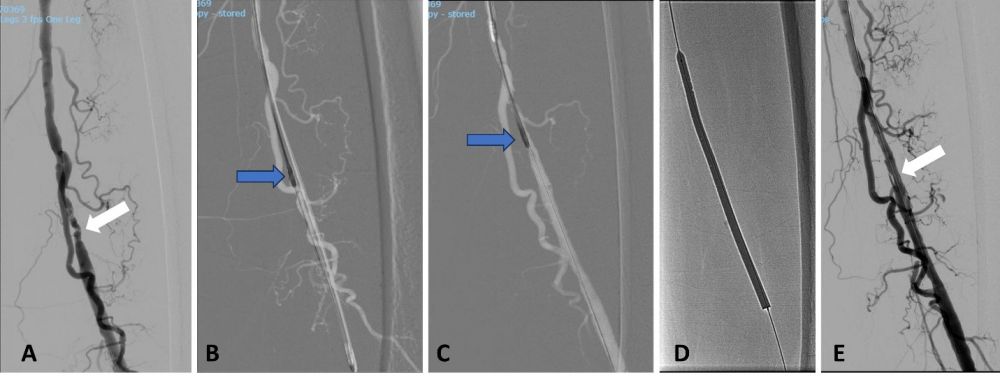

Hình 3. Can thiệp nội mạch khoan phá mảng xơ vữa ở bệnh nhân trên. (A) Chụp động mạch số hoá xoá nền: hẹp nặng khẩu kính động mạch đùi nông (mũi tên trắng). (B, C): Mũi khoan được đưa vào lòng mạch theo dây dẫn và thực hiện khoan phá mảng xơ vữa tại vị trí hẹp. (D) Sau khi khoan phá mảng xơ vữa, đoạn hẹp được nong bổ sung bằng bóng phủ thuốc. (E) Chụp động mạch kiểm tra: khẩu kính động mạch đùi được cải thiện rõ rệt, xuất hiện thêm nhiều nhánh động mạch bên. Bệnh nhân không cần phải đặt stent.